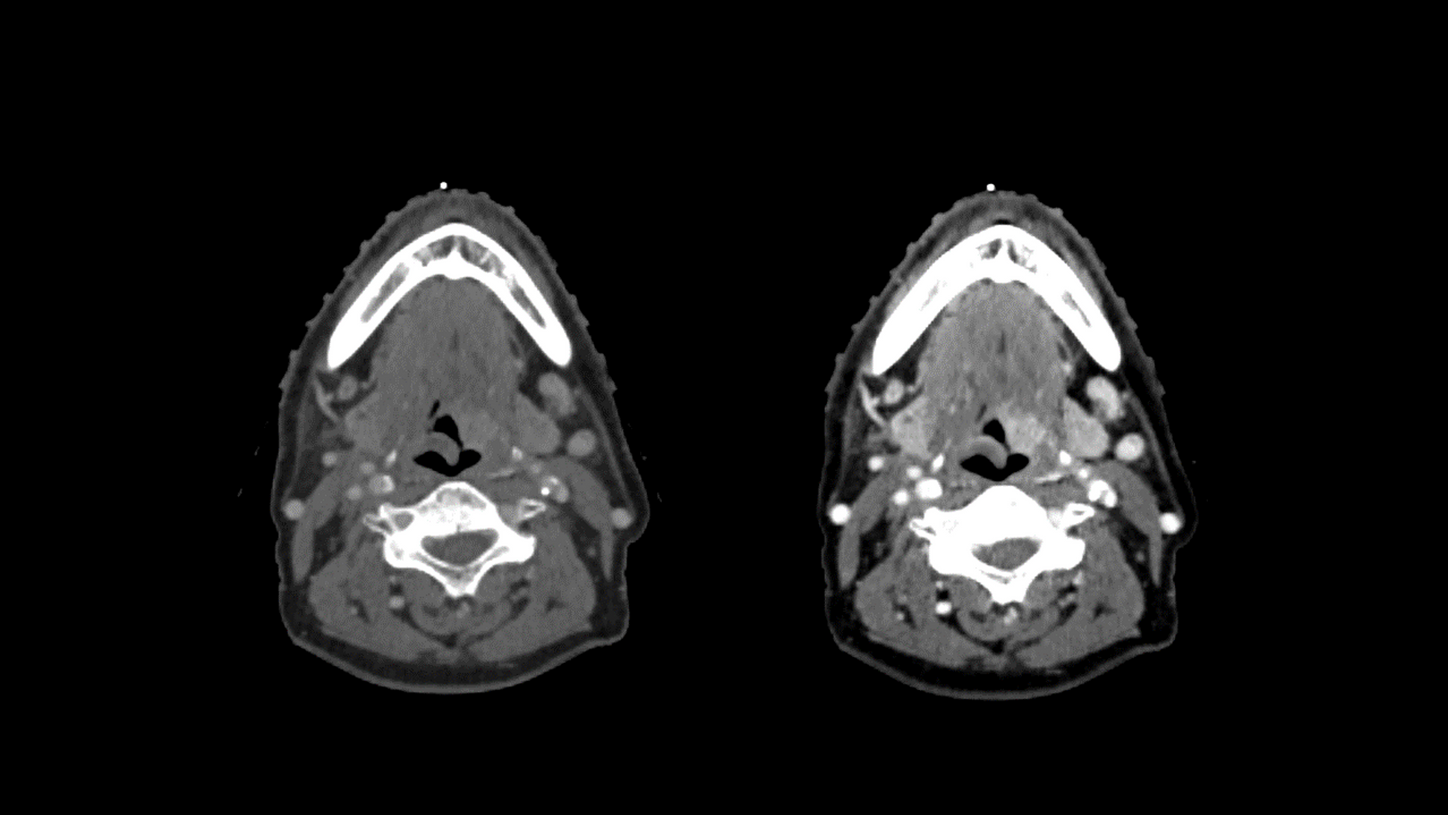

Computed Tomography for Radiation Therapy